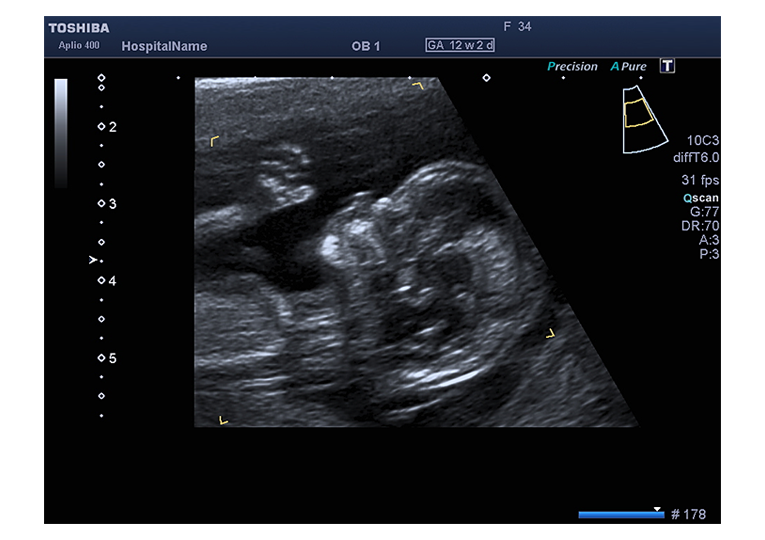

Schon sehr früh in der Schwangerschaft (zwischen 11+0 und 13+6 Schwangerschaftswoche) kann mittels hochauflösender Ultraschallgeräte eine detaillierte Untersuchung Ihres Kindes erfolgen.

Bei dieser Nackentransparenz handelt es sich um eine Flüssigkeitsansammlung im Nacken des Feten, welche bei jedem Kind mehr oder weniger in dieser Phase der Schwangerschaft auftritt. Je nach Grösse des Kindes sind 0,8 bis 2,5 mm „Nackentransparenz“ normal. Eine Verbreiterung dieser „Nackentransparenz“ kann ein Hinweis auf eine Chromosomenstörung, einen Herzfehler oder eine andere Erkrankung des Feten sein. Jedoch können auch gesunde Kinder eine verbreiterte Nackentransparenz aufweisen. Es sind oft nur wenige zehntel Millimeter, um welche die Nackentransparenz bei einem „auffälligen“ Kind vergrößert ist. Daher ist für die Messung ein gutes Ultraschallgerät, Erfahrung und eine spezielle Ausbildung nötig. Generell gilt jedoch: Je breiter die Nackentransparenz, je größer die Wahrscheinlichkeit für ein genetisch oder organisch erkranktes Kind.